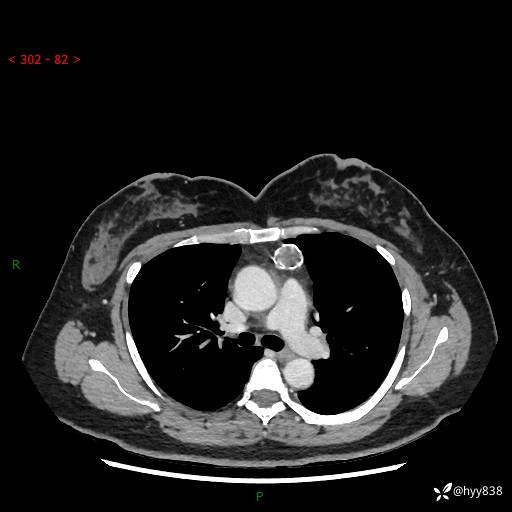

中年女性,检查发现纵隔占位3月余。圆圆的肿物,周围环绕一圈钙化---结果公布~

主诉:检查发现纵隔占位3月余。

现病史:患者于3月前体检行胸部CT检查发现纵隔占位,患者平素无明显咳嗽咳痰,无心慌、胸闷、胸痛、呼吸困难、低热、盗汗,无头痛、头晕,无腹痛、腹胀等不适。现患者欲求进一步治疗,遂来我院就诊,以“纵隔占位”收入我科。 患者自起病以来,精神可,睡眠可,饮食可,大小便正常,体重无明显改变。

胸部CT平扫+增强